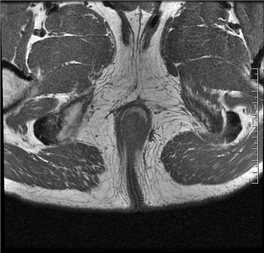

(MRI影像示意图,展示肛瘘常见表现)

在MRI图像中:

◆ 活动期肛瘘MR常表现为T2WI高信号,增强明显强化;

◆ 寻找内口以T1WI增强序列最佳,其次为T2WI抑脂序列,内口影像表现为括约肌内点状T2WI高信号,明显强化或括约肌受牵拉,括约肌间隙消失;

◆ 直径<1CM为瘘管,瘘道的管径最宽处直径>1CM的局限膨隆为脓肿;

◆ 肛瘘愈合期或慢性期,T2WI常表现为低信号,强化减弱或无强化。